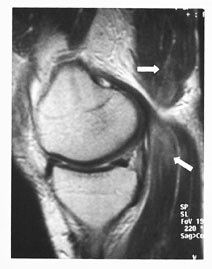

Sener og ligamenter har lavt signal på alle spinnekkosekvenser. Total ruptur vises ved gjennomgående høysignal eller manglende fremstilling av ligament/sene. Partiell ruptur gir et høyt signal i deler av ligament/sene. Imidlertid vil man få en falskt positiv signaløkning på T1-vektet sekvens når lengdeaksen av ligament/sene er 55˚ i forhold til lengdeaksen av magnetfeltet i MR-maskinen (induksjonsfeltet). Dette kalles den magiske vinkel-fenomenet (1). Derfor må man alltid supplere med en T2-vektet sekvens i samme anatomiske retning (fig 1). Årsaken er den tette bindingen mellom vannmolekylene i bruskvevet i ligamenter og sener. Akutt tendinitt vil vises som høysignalområder i senen på T2-vektet sekvens. Kronisk tendinitt vises som breddeøkt sene uten tegn til signaløkning på denne. Akutt-på-kronisk tendinitt diagnostiseres når det er høysignal i en breddeøkt sene.

Rotatorcuffruptur er en samlingsbetegnelse på ruptur av senene til en eller flere av de fire rotatorcuffmusklene. Hyppigst forekommer ruptur av supraspinatussenen, fordi blodforsyningen til muskel-sene-overgangen er dårlig (fig 10). Diagnose av ruptur er den samme som for ligamenter ellers. Partielle rupturer fra undersiden kan være vanskelig å diagnostisere ved MR. MR-artrografi vil vise kontrastutsiving inn i senen fra undersiden. Trange forhold for m. supraspinatus og sene lar seg lett diagnostisere ved en skrå sagittal sekvens. Da får man fremstilt den akromio-klavikulære buen på en ideell måte. Det skal bemerkes at det er andre årsaker til såkalt innklemmingssyndrom enn trange forhold, som for eksempel periartikulære ganglier (fig 11).

Ved spørsmål om instabilitet eller residiverende luksasjoner, utføres en MR-artrografi. Man ser etter forandringer i labrum, fossa glenoidalis, kapsel med ligamenter og caput humeri. I tillegg til de vanlige projeksjonene utføres også en såkalt ABER (abduksjon ekstern rotasjon)-projeksjon (9) (fig 12). Pasienten ligger med armen rotert over hodet. Snittene legges parallelt med lengdeaksen av humerusdiafysen. De fremre strukturer blir dermed lagt i strekk og patologiske forhold blir synlige (fig 12).